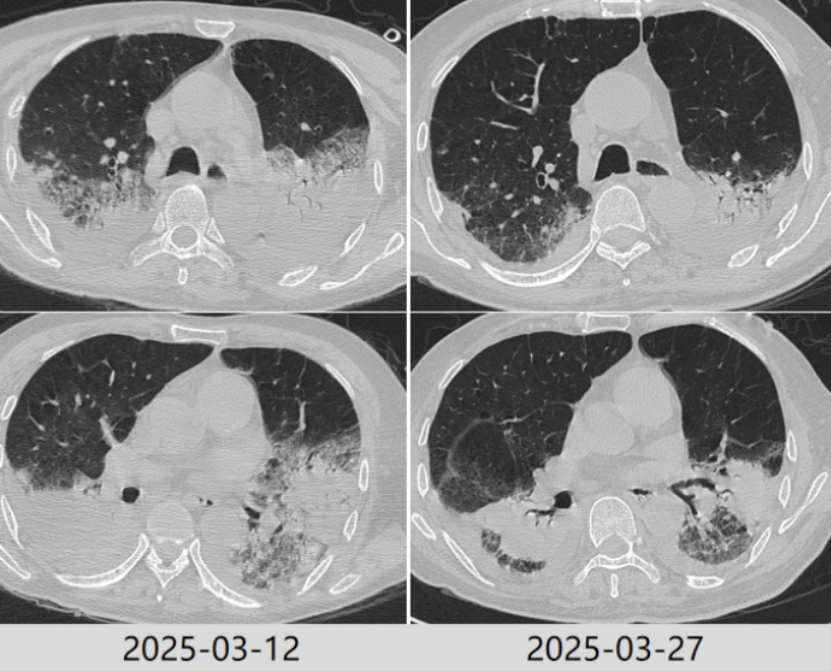

2025年3月5日复查胸部CT病灶较前进展(图4),炎症指标有所回弹,以中性粒细胞升高为主,抗感染方案调整为哌拉西林他唑巴坦4.5 g q9h+奥马环素300 mg qd po。

图4 患者复查胸部CT对比

2025年3月12日患者氧合无明显改善,复查胸部CT示肺部病灶进展(图4)。将抗生素方案调整为美罗培南+米卡芬净+莫西沙星,甲泼尼龙抗炎,无创呼吸机辅助通气。

根据病原学结果,先后予以米卡芬净+美罗培南、哌拉西林他唑巴坦+环丙沙星、头孢他啶阿维巴坦抗感染治疗。2025年3月24日拔管。3月27日复查胸部CT提示肺部病变好转吸收(图5)。患者仍有明显咳痰困难,乏力,四肢肌力下降,经康复锻炼恢复欠佳。

图5 复查胸部CT对比